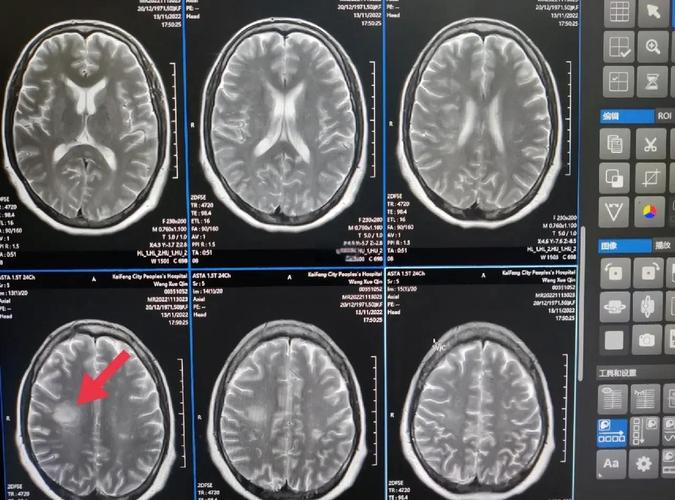

- 立即进行下一步检查:为了明确诊断,医生会安排头颅磁共振(MRI),特别是DWI(弥散加权成像)序列。

- MRI对早期脑梗极其敏感:发病后30分钟到2小时,DWI序列就能显示出梗死的病灶,像一个“亮点”,非常清晰。

- MRI是诊断早期脑梗的“金标准”。